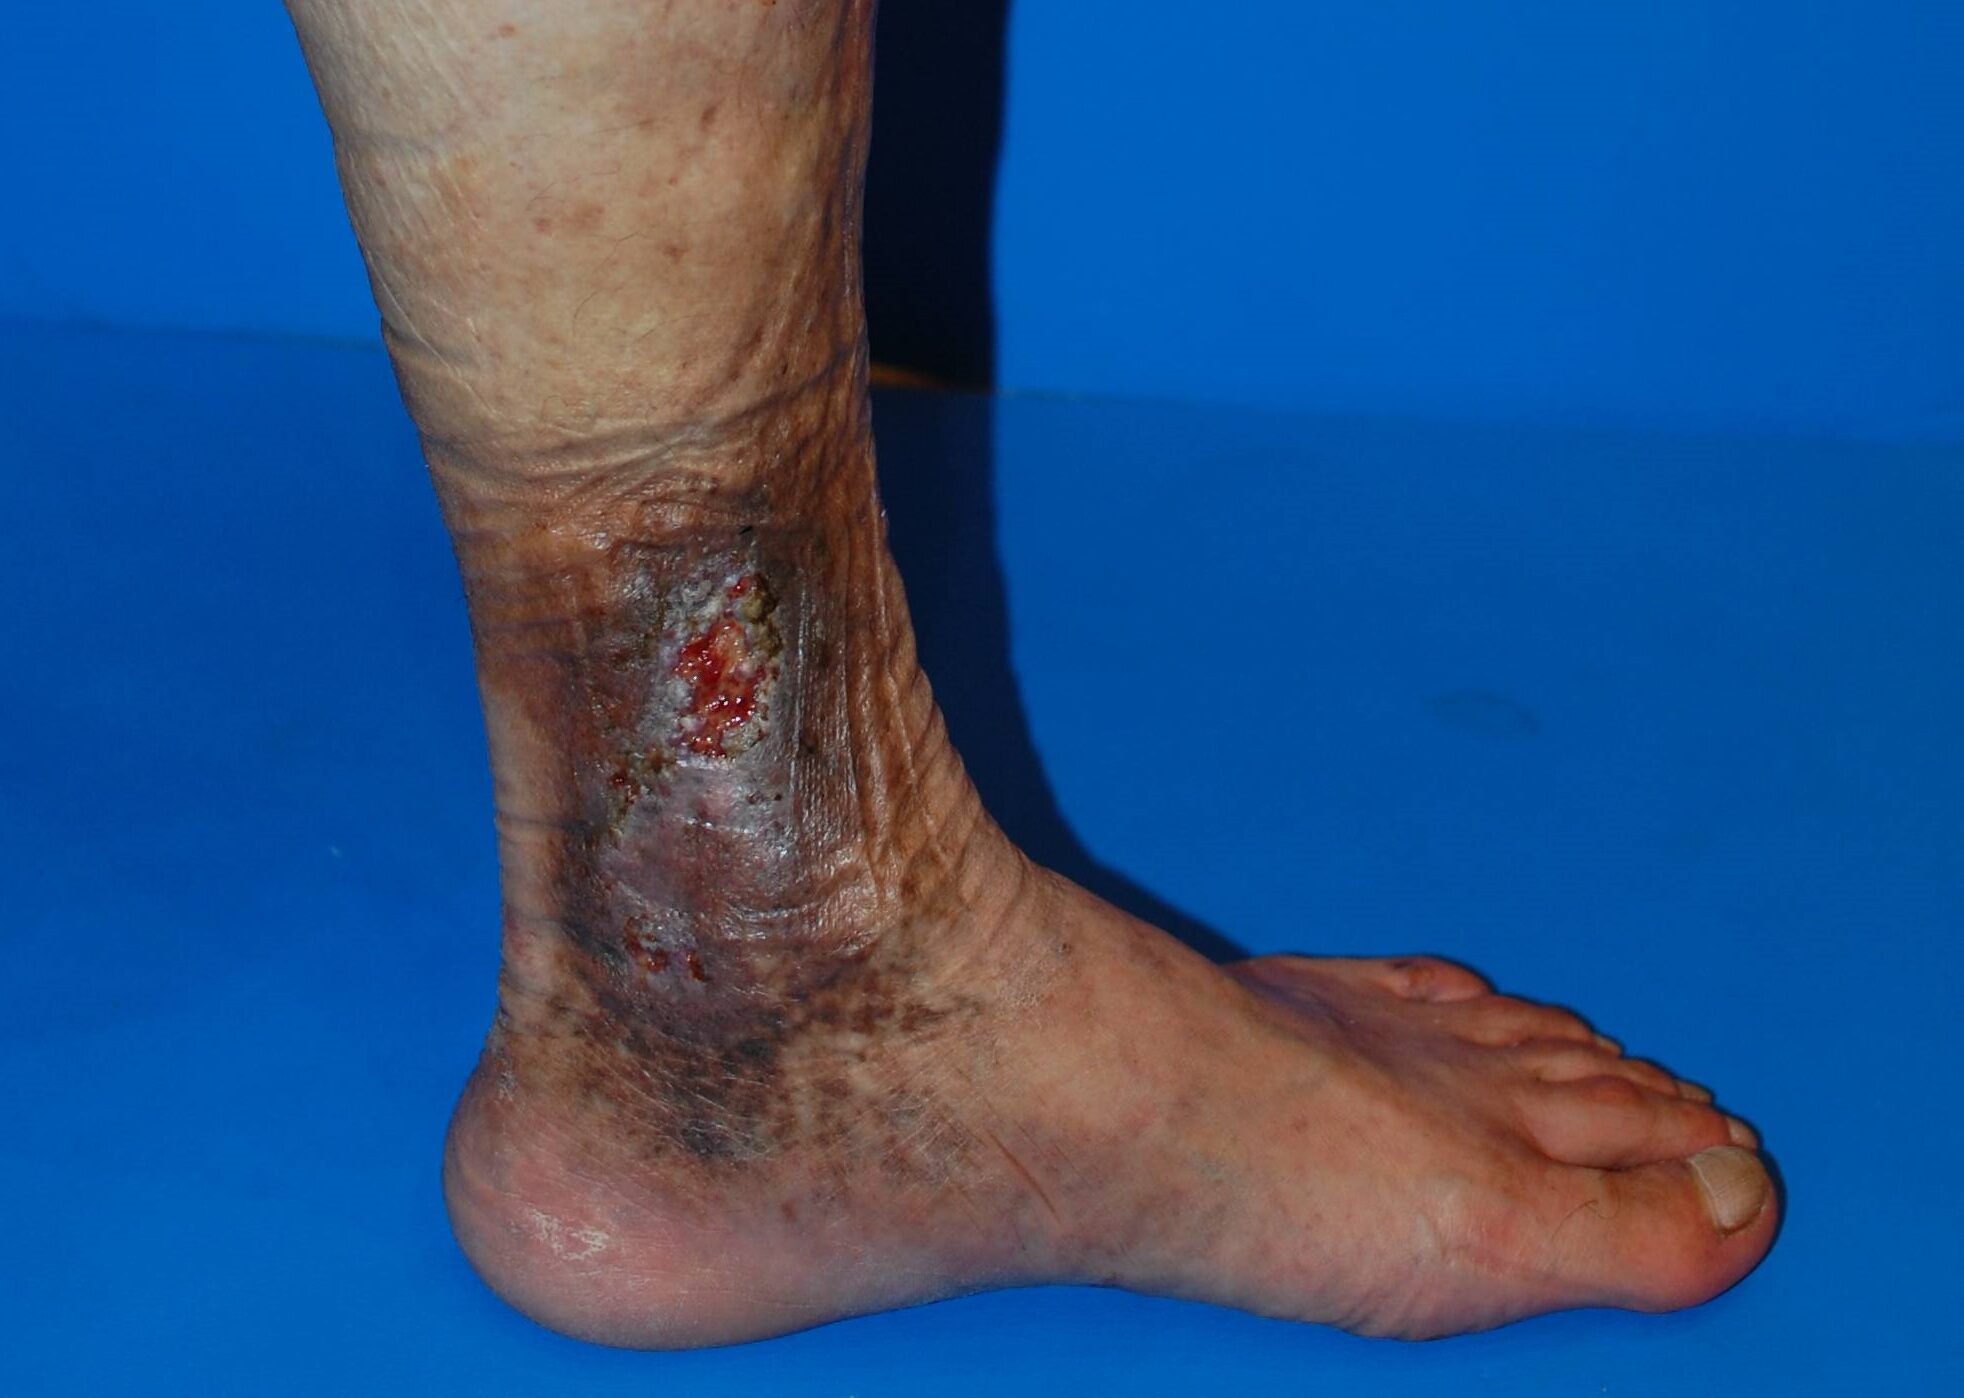

【ステップ4】皮膚潰瘍 ― 最終段階。強い痛みと治りにくい傷

皮膚が破れ、大きな傷となります。

- 少しの刺激で皮膚が裂ける

- 滲出液が出て、治っても再発しやすい

- 治癒まで数ヶ月〜数年かかることも

皮膚潰瘍

生活に大きな支障が出るため、早期治療でここまで進行させないことが重要です。